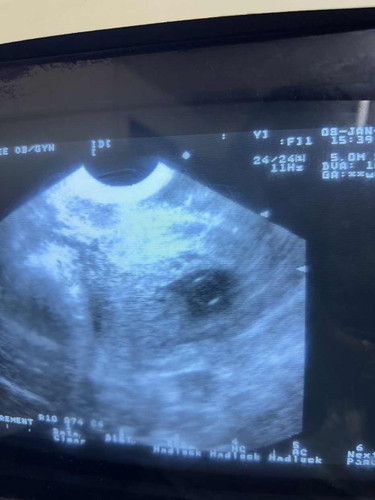

เพิ่งไปหาหมอมาเมื่อวานค่ะครรภ์ได้ 11 สัปดาห์คุณหมอคลินิกแรกแจ้งว่าเป็นครรภ์ไข่ปลาอุก ไม่มีตัวอ่อนอยู่ในท้อง ซาวด์ผ่านหน้าท้อง คุณหมอแจ้งให้ไปขูดมดลูก คุณแม่เลยไม่สบายใจไปอีกคลินิกใหม่ซาวผ่านช่องคลอด เห็นก้อนกลมเหมือนในรูป คุณหมอแจ้งว่าอีกอาทิตย์นึงมาตรวจใหม่ว่าใช่ตัวเด็กไหม คุณแม่คนไหนเคยเจอเหตุการณ์แบบนี้บ้างคะตอนนี้คุณแม่ไม่สบายใจมาก ไม่รู้เลยว่าตัวเองท้องหรือไม่ท้อง

ในใบอัลตร้าซาวด์ขึ้น11wซึ่งเชื่อถือได้ แสดงว่าเห็นตัวอ่อน หมอไว้วัดคลื่นหัวใจเด็กไหมค่ะจากการซาวครั้งนี้ เครื่องมืออาจทำให้เห็นน้องไม่ชัด บ้านนี้9wชัดเจน